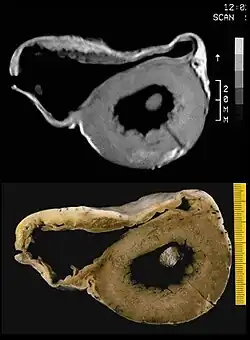

In vitro MRI and corresponding cross section of the heart in ARVD show RV dilatation with anterior and posterior aneurysms (17-year-old asymptomatic male athlete who died suddenly during a soccer game).

Fatty infiltration of the RV free wall can be visible on cardiac MRI. Fat has increased intensity in T1-weighted images. However, it may be difficult to differentiate intramyocardial fat and the epicardial fat that is commonly seen adjacent to the normal heart. Also, the sub-tricuspid region may be difficult to distinguish from the atrioventricular sulcus, which is rich in fat.

Cardiac MRI can visualize the extreme thinning and akinesis of the RV free wall. However, the normal RV free wall may be about 3 mm thick, making the test less sensitive.